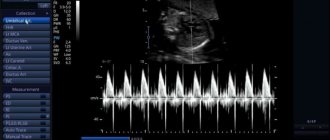

Докторами всего мира для диагностики различных заболеваний используются пальпация, перкуссия и аускультация. При беременности,